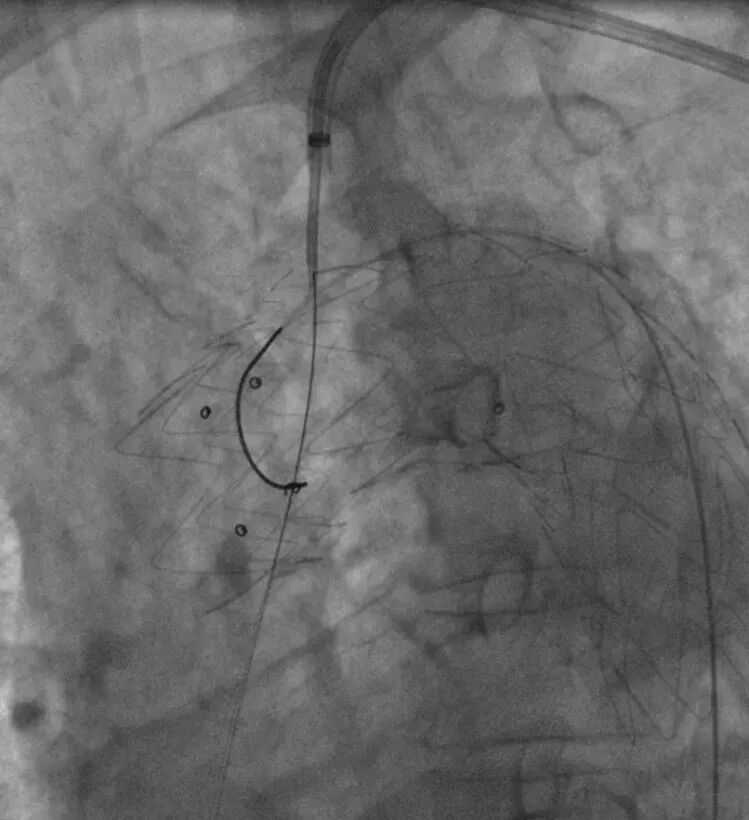

3. 经左肱动脉鞘管引入单弯导管,头端正对于主动脉弓处覆膜支架,置入250T导丝并配合单弯导管,顺利在左锁骨下动脉根部处原位开窗,手推造影明确导丝已进入覆膜支架。

送入单弯导管及250T导丝

250T导丝成功于LSA根部破膜

4. 依次使用3-30mm球囊、8-40mm球囊扩张开窗口;并通过球囊带鞘技术通过主动脉开窗部位。

3-30mm球囊扩张

8-40mm球囊扩张

RAO确认

球囊带鞘进膜